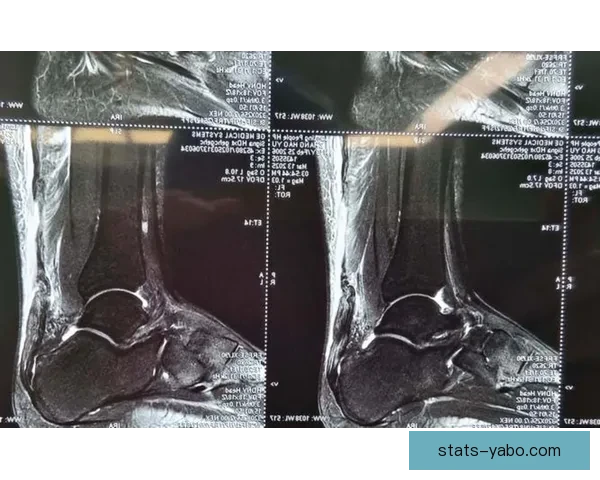

1、髌腱撕裂病理解析髌腱位于膝关节前方,是连接髌骨与胫骨的重要组织结构,承担着膝关节屈伸时的核心力量传导。髌腱撕裂通常由外力冲击或长期高强度训练累积造成,其症状包括膝关节剧烈疼痛、功能受限及肿胀明显。对于职业篮球运动员而言,这种伤病极大影响其弹跳力和急停变向能力。

髌腱撕裂亚博体育平台可分为部分撕裂和完全撕裂两类,穆迪此次受伤被确诊为完全撕裂,这意味着髌腱的纤维组织已经断裂,需要通过手术进行修复。手术后,患者通常会经历长达数月的功能恢复期,期间需要循序渐进地恢复肌肉力量和关节灵活性。